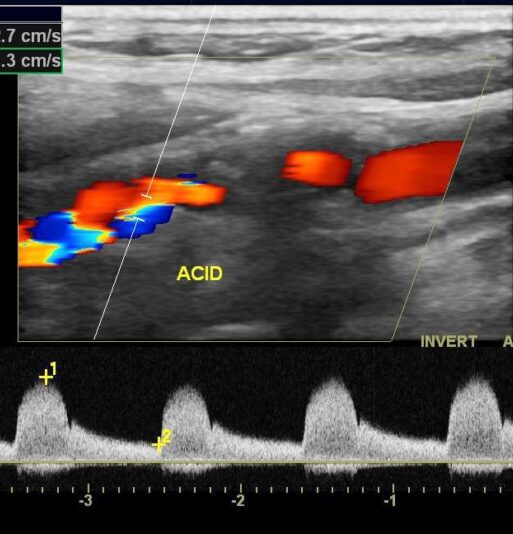

Este curso presencial oferece uma abordagem abrangente, com foco nos conhecimentos essenciais sobre a anatomia hemodinâmica e as principais patologias associadas a esse território vascular.

Os participantes terão a oportunidade de explorar a prática da ecografia Doppler em profundidade.

O conteúdo foi cuidadosamente estruturado para garantir uma experiência completa, que une teoria e prática, preparando os médicos para utilizar essa importante ferramenta diagnóstica com segurança e precisão em sua rotina clínica.